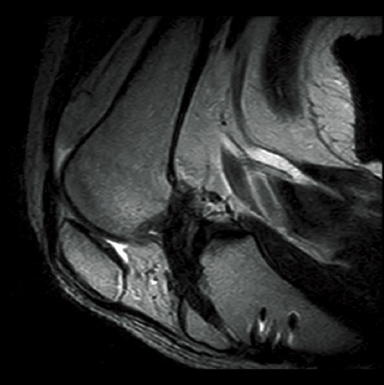

FatSep-T2WI